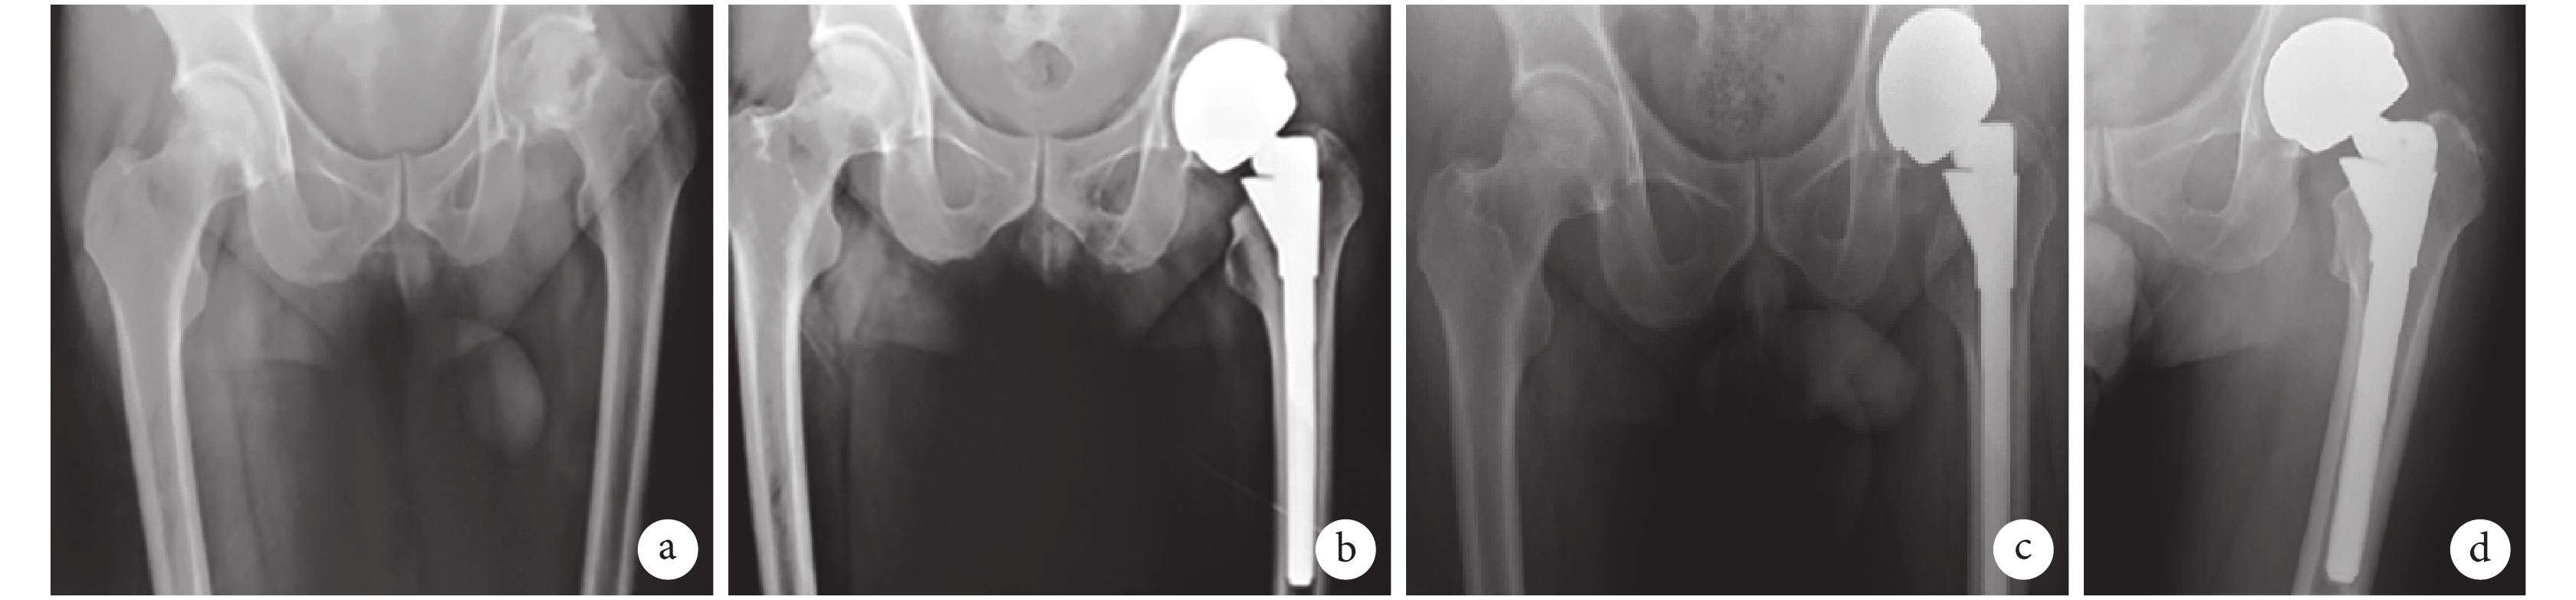

X 線片復查示,本組髖臼外展角及前傾角分別為 (46.5±3.2)、(14.8±3.6)°,均在安全區范圍[14]內;股骨柄假體初始穩定質量按照 Mulliken 等[6]標準評定,獲優 39 髖、良 4 髖。隨訪期間,2 例(2 髖,4.7%)發生骨溶解,其中 1 例(1 髖,2.3%)于術后 3 年出現手術側腹股溝和大腿疼痛,進行性加重至不能行走,X 線片顯示股骨距區呈進行性骨溶解伴骨缺損,股骨柄假體周圍(Gruen Ⅰ、Ⅱ區和Ⅳ、Ⅶ區)X 線透亮帶呈進行性增寬,金屬臼杯也呈輕度上移,診斷為假體松動伴骨缺損,行二期翻修術。另 1 例患者術后 3 年于股骨距區(GruenⅠ區)出現骨溶解和缺損,患者未出現疼痛不適等松動癥狀,未作特殊處理。其余患者假體無松動、下沉,假體與骨組織固定界面均為骨性固定,無進行性骨溶解征象。見圖 1。

a. 術前;b. 術后 2 d;c. 術后 6 個月;d. 術后 8 年

Figure1. X-ray films of a 61-year-old male patient with the osteonecrosis of the left femoral head who was treated with large-head metal-on-metal THAa. Before operation; b. At 2 days after operation; c. At 6 months after operation; d. At 8 years after operation